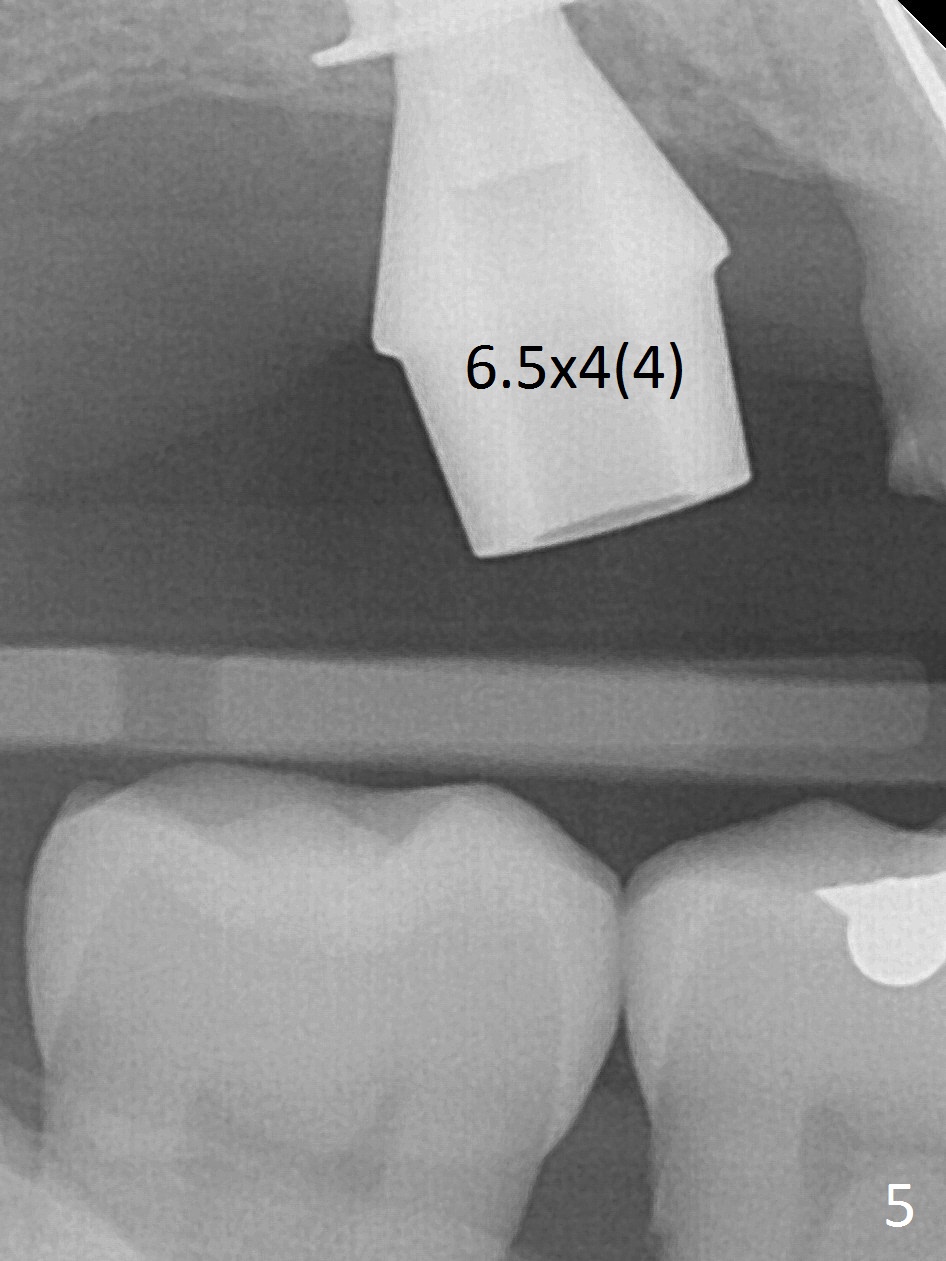

Since the ridge is wide at the site of #2, Magic Split is used for access (flapless) and bone expansion. The bone is so soft that there is no resistance until 4.3 mm Magic Expander is used for 9 mm (Fig.6). A 5 mm tap drill is stable (Fig.1), so are a 5.5x9 mm dummy implant (Fig.2) and a 6x9 mm IBS implant (Fig.3 (<: sinus lift)). In fact the distal thread is still supracrestal (Fig.4 (BW)). After additional 2 mm placement, the distal thread is subcrestal (Fig.5); the mesial margin of a 6.5x4(4) mm abutment is subgingival. A longer cuff (5 mm instead of 4 mm) is more favorable for future restoration. At present the abutment (Fig.7) as well as the tooth #3 with rugged surfaces is used to hold periodontal dressing in place. The abutment margin is completely subgingival 3 months postop (Fig.8 (white dashed line: gingival margin)). It appears that the implant is placed ~ 1 mm deeper than ideal (Fig.9). Diode laser is used for gingivectomy prior to impression. The abutment screw becomes loose 2 months post cementation. After retightening, occlusal equilibrium is conducted with 3 layers of articulating paper. Night guard is provided. The crown/abutment dislodges 1 year 2 months later. Since the gingiva is erythematous, a 6x7 mm healing abutment is placed (Fig.10). The implant seems to have been placed too deep and palatal. It appears that an abutment driver should be buried to prevent the screw re-loosening. Guided surgery should have been done.